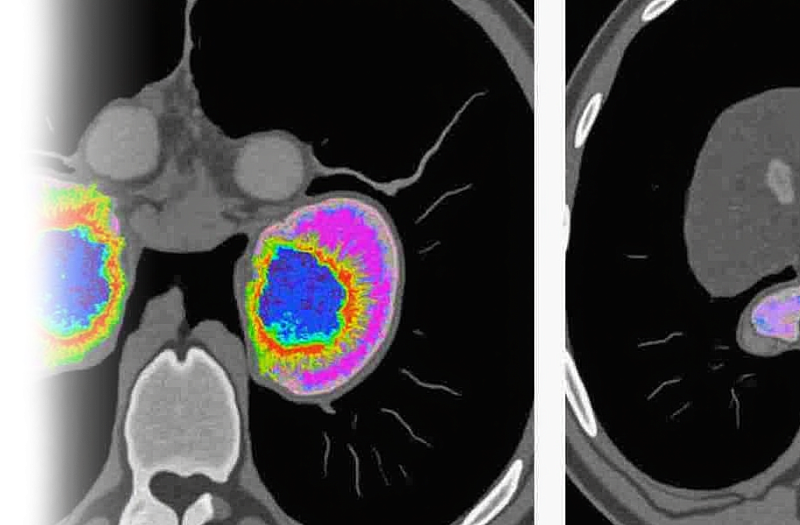

Компьютерная томография почек и надпочечников – важный метод прицельного исследования состояния почек и надпочечников.

Как проводится КТ почек и надпочечников?

После этого пациент ложится на стол сканера, который постепенно перемещается в аппарат. Во время сканирования следует лежать неподвижно, чтобы получаемые трехмерные изображения были четкими и неискаженными.